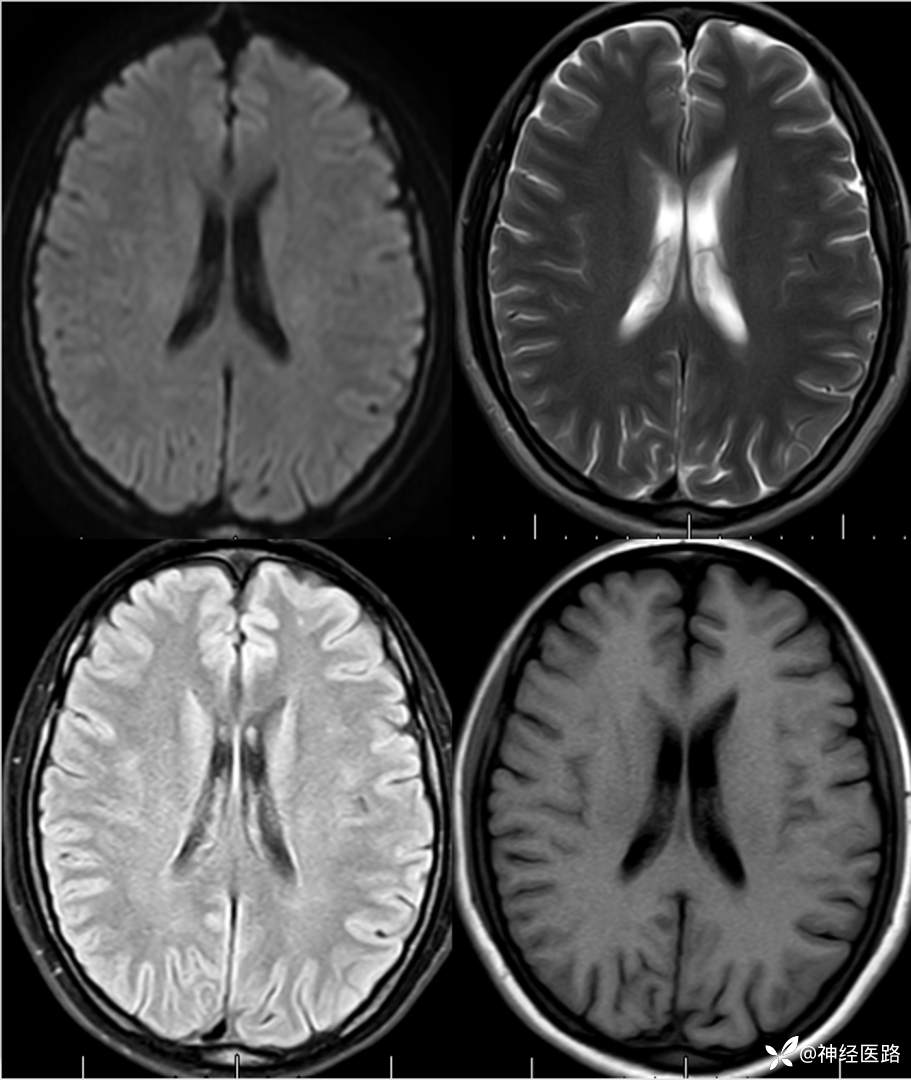

辅助检查:头部磁共振: 1.左侧额叶及右侧顶叶白质内高信号,请结合临床及相关检查。2.双侧小脑半球脑萎缩。3.部分颅骨信号增高。